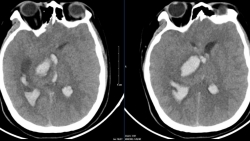

Dị dạng mạch máu não – Kẻ giết người thầm lặng

Nhiều bệnh nhân ở tuổi còn rất trẻ bị tử vong hoặc để lại di chứng nặng nề khi chỉ xuất hiện một số cơn đau đầu. Nguyên nhân là do dị dạng mạch máu não.